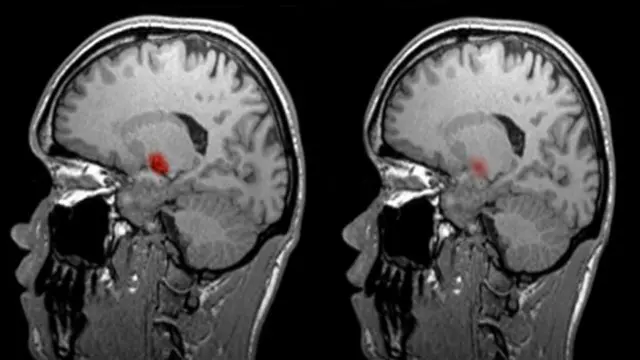

Bu taramada beyindeki oksijen değişimi hareket halinde görebiliyor. Beynin bir kısmı belli bir iş üzerinde yoğunlaşmışsa, örneğin kelime ya da dille ilgili bir çalışma yapılıyorsa o bölgede enerji kullanıldığı için kan akışı artmaktadır. İşte fMRI tarayıcısı bu kan akışını gözler.

Yapılan işe göre beynin aktif olan kısımlarındaki renk değişimini tarama sırasında ekranda görmek mümkün oluyor.

Örneğin ne söyleyeceğinizi düşünürken beynin farklı bir bölgesi, sayı sayma gibi düşünme gerektirmeyen monoton bir işlemde farklı bir bölge aktif hale gelir.

Fakat bir iş yaparken beynin hangi bölgesinin aktif hale geldiğini görmek ile beyin taraması yoluyla düşünceyi okumak aynı şey değildir elbette.

Yine de bu tür taramalar beyni anlama bakımından devrime yol açtı.

Daha önceleri doktorların tek bilgisi beyninde hasar olan bir hastanın sorununun nerede olduğu ve bunun ne tür bir arızaya yol açtığından ibaretti. Fakat beyin taraması sayesinde nörologların sağlıklı bir beyni görüp farklı kısımlarının nasıl kullanıldığını ve aralarındaki ilişkiyi anlaması mümkün oluyor.